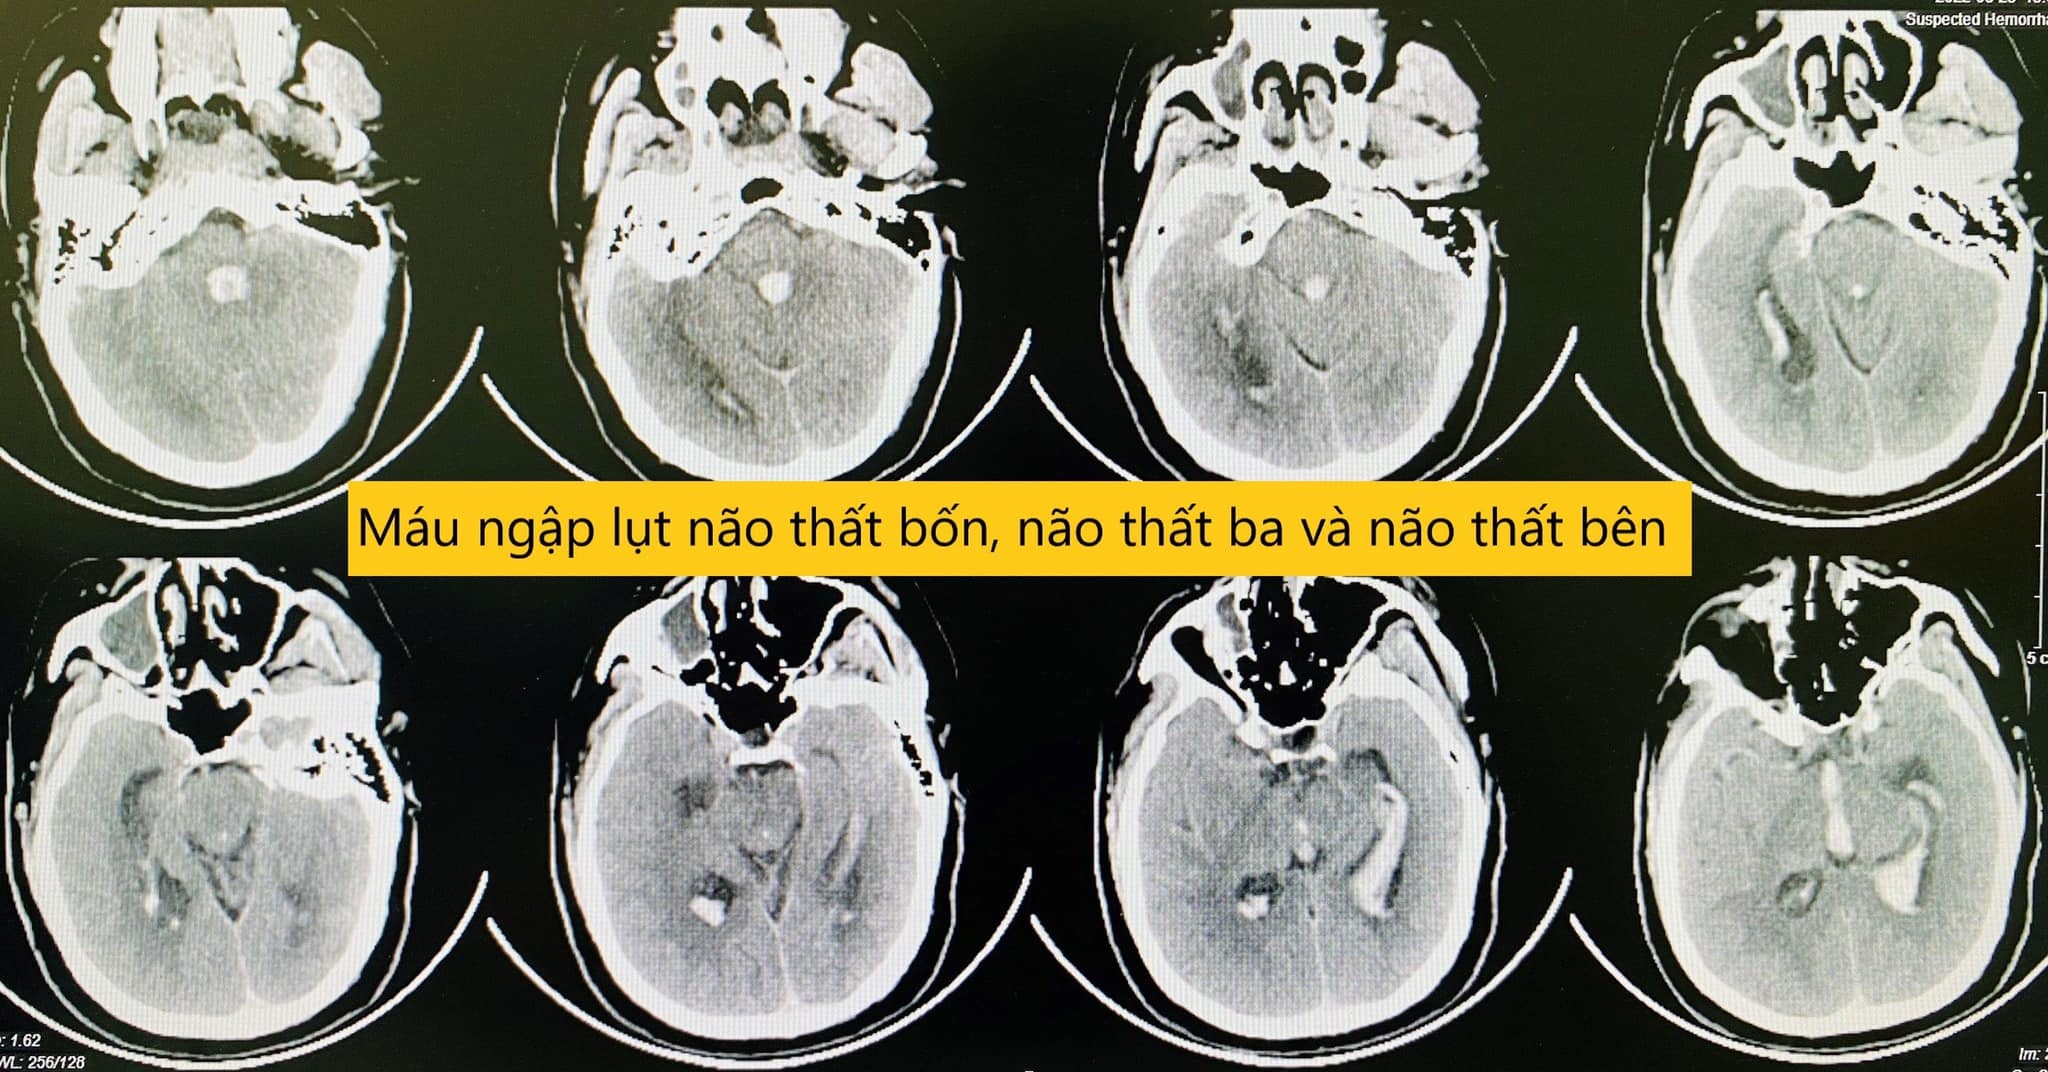

Hình ảnh chảy máu toàn bộ não thất bên, não thất ba, não thất tư của bệnh nhân. Ảnh: BVCC.

Kết quả chụp phim sọ não cho thấy tình trạng chảy máu toàn bộ não thất bên, não thất ba, não thất bốn gây giãn não thất cấp, gây tắc nghẽn sự lưu thông hệ thống não thất.

"Với mức độ tổn thương này, nếu không can thiệp, bệnh nhân chắc chắn sẽ tử vong", bác sĩ Trung tâm Đột quỵ cho biết.